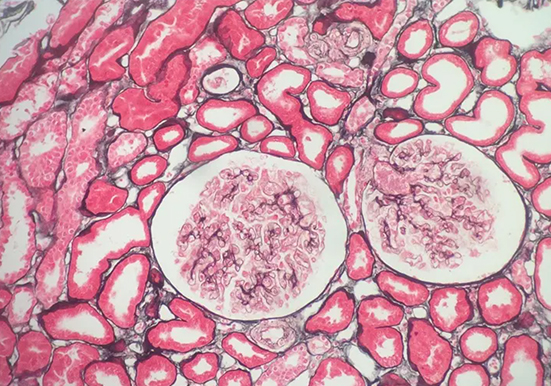

福州组织病理学实验